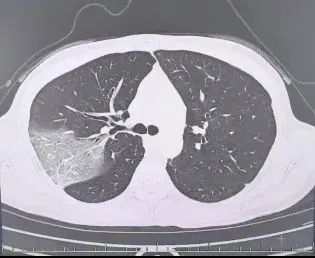

连续坚持三天后病情加剧,她在会议上频繁咳嗽,呼吸急促,体温攀升至39.7℃。同事紧急将她送回医院,发现她的多片肺叶呈现“白肺”症状,多项生理指标异常,最终被确诊为重症流感。

病毒性肺炎可由流感病毒引起,亦可能继发于细菌感染。此病症常伴有高烧、干咳等典型症状,病情严重时可能导致呼吸功能衰竭。程女士所患的“白肺”即为流感病毒导致的肺部感染严重病例。